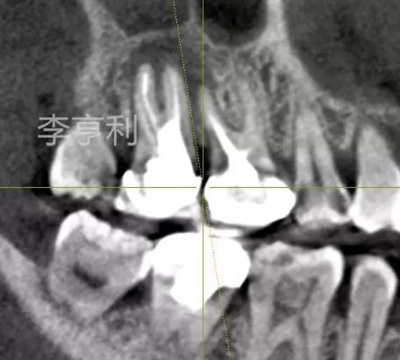

【輔助檢查】: CBCT見(jiàn)17冠部大面積充填物阻射影,接近髓室底,根管內(nèi)充填物錐度尚可,距根尖均為2mm以?xún)?nèi),根尖周大范圍阻射影主要在頰根區(qū)域,波及16的DB根尖區(qū)域,頰腭側(cè)骨板完整